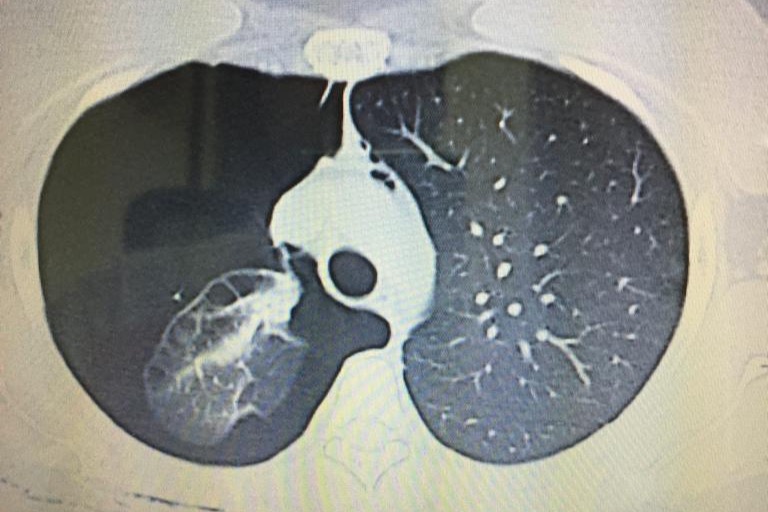

Dos semanas atrás nuestra querida Gaby tuvo dificultad para respirar. Jorgito la llevo a una clínica en Guarenas y fue diagnosticada con una "enfermedad bulosa pulmonar complicada con neumotorax derecho activo". Traduzco: una de las capas de tejido de su pulmón derecho tiene una condición donde se crea una burbuja de aire por dentro, comprimiendo el pulmón y limitando su expansion al momento de inhalar. En la clínica donde fue atendida, le hicieron un procedimiento sencillo que consta de insertar una suerte de manguera por el abdomen hasta el pulmón, y con ella extraer el vacío creado por la burbuja y lograr estabilizar su movimiento natural de expansion y retracción, con la finalidad de llevar su capacidad pulmonar de nuevo a un 100%. Este tratamiento duro 3 días y les costo poco mas de $2,000.

Lamentablemente, el día de ayer, luego de hacer examen post-operatorios para comprobar que no había reincidencia de la burbuja de aire, se percataron que su capacidad pulmonar había disminuido considerablemente de nuevo a menos de un 50%, por lo que la condición requeriría de una cirugía mas complicada y delicada. Esta nueva intervención consiste en abrir el tórax para tener acceso completo al pulmón, remover la capa de tejido que esta dañada, y proceder a cocer nuevamente el pulmón y su pecho. Tiene una duración de dos horas y posteriormente necesita estar hospitalizada tres días.

Two weeks ago our beloved Gaby started having some breathing difficulties. Jorge took her to a clinic and she was later diagnosed with "pulmonary bullous disease complicated with active right pneumothorax". I'll explain: one of the outer tissue layers of her right lung developed a condition where it creates an inner air bubble, compressing the lung space and limiting its expansion when inhaling. She went under surgery at the hospital that day, where they basically put a sort of hose in her abdomen until her lung to be able to reduce the pressure of the bubble and extract the air trapped in it to restore lung capacity to 100%. This procedure took three days for completion and cost them $2,000.

Regrettably, yesterday, after the post-surgery tests meant to reassure that the issue was corrected and the lung activity restored, they found out her lung capacity went back down to under 50%, and a more complicated surgery is now needed. This time around, they need to open up her thorax to be able to fully access her lung, then they have to cut off the outer damaged layer and stitch back both her lung and her chest. This procedure lasts about two hours and she needs to be hospitalized for three days after.

Dos semanas atrás nuestra querida Gaby tuvo dificultad para respirar. Jorgito la llevo a una clínica en Guarenas y fue diagnosticada con una "enfermedad bulosa pulmonar complicada con neumotorax derecho activo". Traduzco: una de las capas de tejido de su pulmón derecho tiene una condición donde se crea una burbuja de aire por dentro, comprimiendo el pulmón y limitando su expansion al momento de inhalar. En la clínica donde fue atendida, le hicieron un procedimiento sencillo que consta de insertar una suerte de manguera por el abdomen hasta el pulmón, y con ella extraer el vacío creado por la burbuja y lograr estabilizar su movimiento natural de expansion y retracción, con la finalidad de llevar su capacidad pulmonar de nuevo a un 100%. Este tratamiento duro 3 días y les costo poco mas de $2,000.

Lamentablemente, el día de ayer, luego de hacer examen post-operatorios para comprobar que no había reincidencia de la burbuja de aire, se percataron que su capacidad pulmonar había disminuido considerablemente de nuevo a menos de un 50%, por lo que la condición requeriría de una cirugía mas complicada y delicada. Esta nueva intervención consiste en abrir el tórax para tener acceso completo al pulmón, remover la capa de tejido que esta dañada, y proceder a cocer nuevamente el pulmón y su pecho. Tiene una duración de dos horas y posteriormente necesita estar hospitalizada tres días.

Two weeks ago our beloved Gaby started having some breathing difficulties. Jorge took her to a clinic and she was later diagnosed with "pulmonary bullous disease complicated with active right pneumothorax". I'll explain: one of the outer tissue layers of her right lung developed a condition where it creates an inner air bubble, compressing the lung space and limiting its expansion when inhaling. She went under surgery at the hospital that day, where they basically put a sort of hose in her abdomen until her lung to be able to reduce the pressure of the bubble and extract the air trapped in it to restore lung capacity to 100%. This procedure took three days for completion and cost them $2,000.

Regrettably, yesterday, after the post-surgery tests meant to reassure that the issue was corrected and the lung activity restored, they found out her lung capacity went back down to under 50%, and a more complicated surgery is now needed. This time around, they need to open up her thorax to be able to fully access her lung, then they have to cut off the outer damaged layer and stitch back both her lung and her chest. This procedure lasts about two hours and she needs to be hospitalized for three days after.